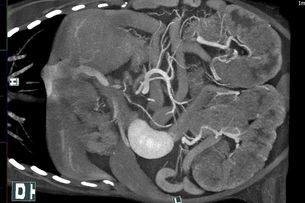

scan2